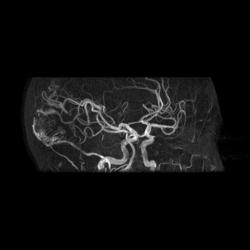

Артерио-венозная мальформация сосудов головного мозга.

3D TOF

При МР-ангиографии в режиме 3D TOF и 2D-TOF SPGR без применения контрастирующих веществ:

- определяется клубок расширенных и извитых патологических сосудов, получающих артериальную кровь из средней оболочечной артерии (ветвь наружной сонной артерии),  последняя расширена, из средней мозговой артерии и из задней мозговой артерии, эти артерии также шире, чем артерии контрлатеральной стороны. Дренирующие вены впадают в область стока синусов, а также в задний отдел верхнего сагиттального синуса

- дополнительно отмечены расширенные и извитые экстракраниальные сосуды, преимущественно под правой половиной задней черепной ямки.